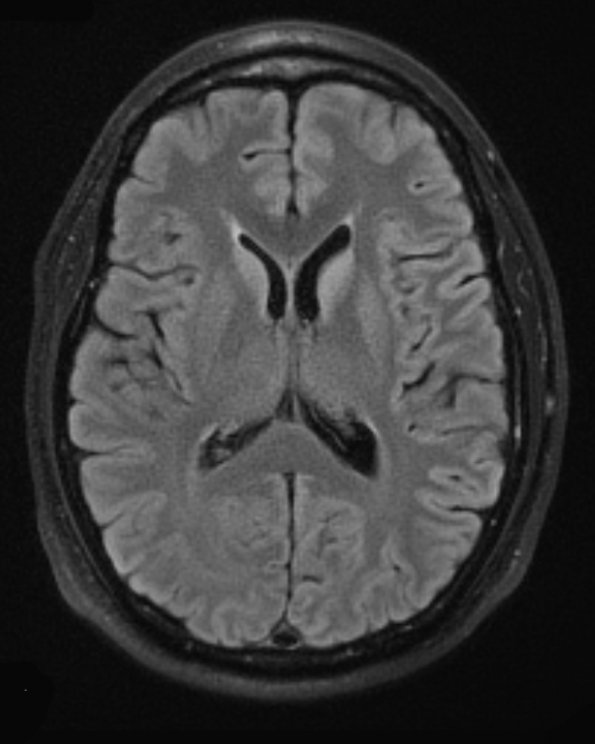

At autopsy the brain is well formed and weighs 1520g. There are no abnormalities present on the cerebral hemispheres. The cerebellum is full and unremarkable. The brainstem has a normal configuration and the cranial nerves are in an appropriate location. There are no abnormalities of the structures at the base of the brain including the vasculature. ---- 18A1 A TIRM Blade study shows hyperintensity of the caudate and, to a lesser extent, putamen and pulvinar.